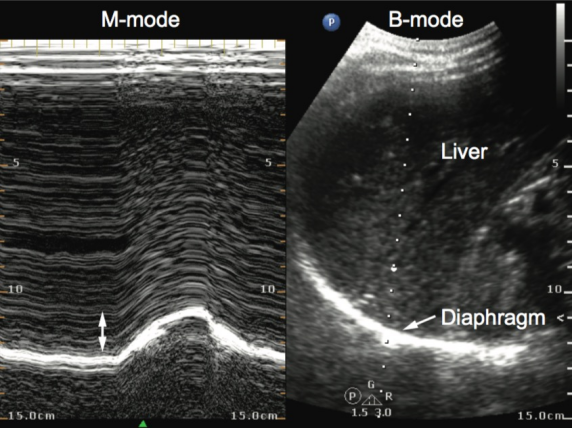

1)膈肌厚度(TDi)测量:膈肌厚度反映膈肌的收缩能力。采用高频线阵探头,置于患者右侧腋前线第810肋间(图1,获取图像(图2分别测量吸气末膈肌厚度(Tdi-insp)与呼气末膈肌厚度(Tdi-exp),重复测量3次取平均值,并计算膈肌增厚分数(DTF),公式为:

2  膈肌厚度图像

2)膈肌移动度(DE)测量:反映膈肌运动的快慢。采用低频凸阵探头,置于右侧肋缘下锁骨中线处(图3,获取图像(图4,测量平静呼吸及深吸气时的膈肌移动度,同样重复测量3次取平均值;亦可通过膈肌移动度与对应时间的比值,计算膈肌收缩速度(DCV)。公式为:DCV=DE/Time。其中,Time为对应运动时间,本质是计算膈肌运动轨迹的斜率。

4  膈肌移动度图像